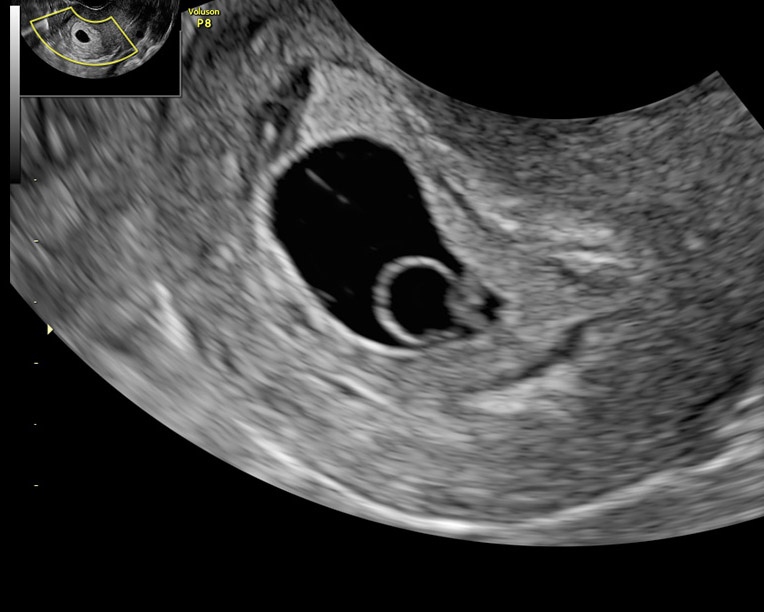

• SonoRenderlive - повышает эффективность 3D и 4D исследований путем автоматического выбора положения плоскости визуализации. Эта функция позволяет получить наиболее четкие и детальные изображения, упрощая процесс работы врача.

• SonoNT и SonoIT - представляют полуавтоматические стандартизированные измерения толщины воротникового пространства и внутричерепного пространства плода в I триместре беременности. Эти измерения являются важными для скрининга на хромосомные аномалии и другие патологии.

Благодаря автоматизированным функциям диагностики, Voluson P8 упрощает процесс работы врача, сокращает время проведения исследований и повышает точность получаемых результатов. Это позволяет врачам более эффективно проводить диагностику и обеспечивать качественное обслуживание пациентов.

• Дополнительные программные опции для объемной реконструкции 3D/4D Activation. Программный пакет 3D/4D Activation включает: режим 3D, режим 4D Realtime, SonoRenderlive – автоматическое определение границ конечностей и лица плода и получение объемного изображения в 3D/4D